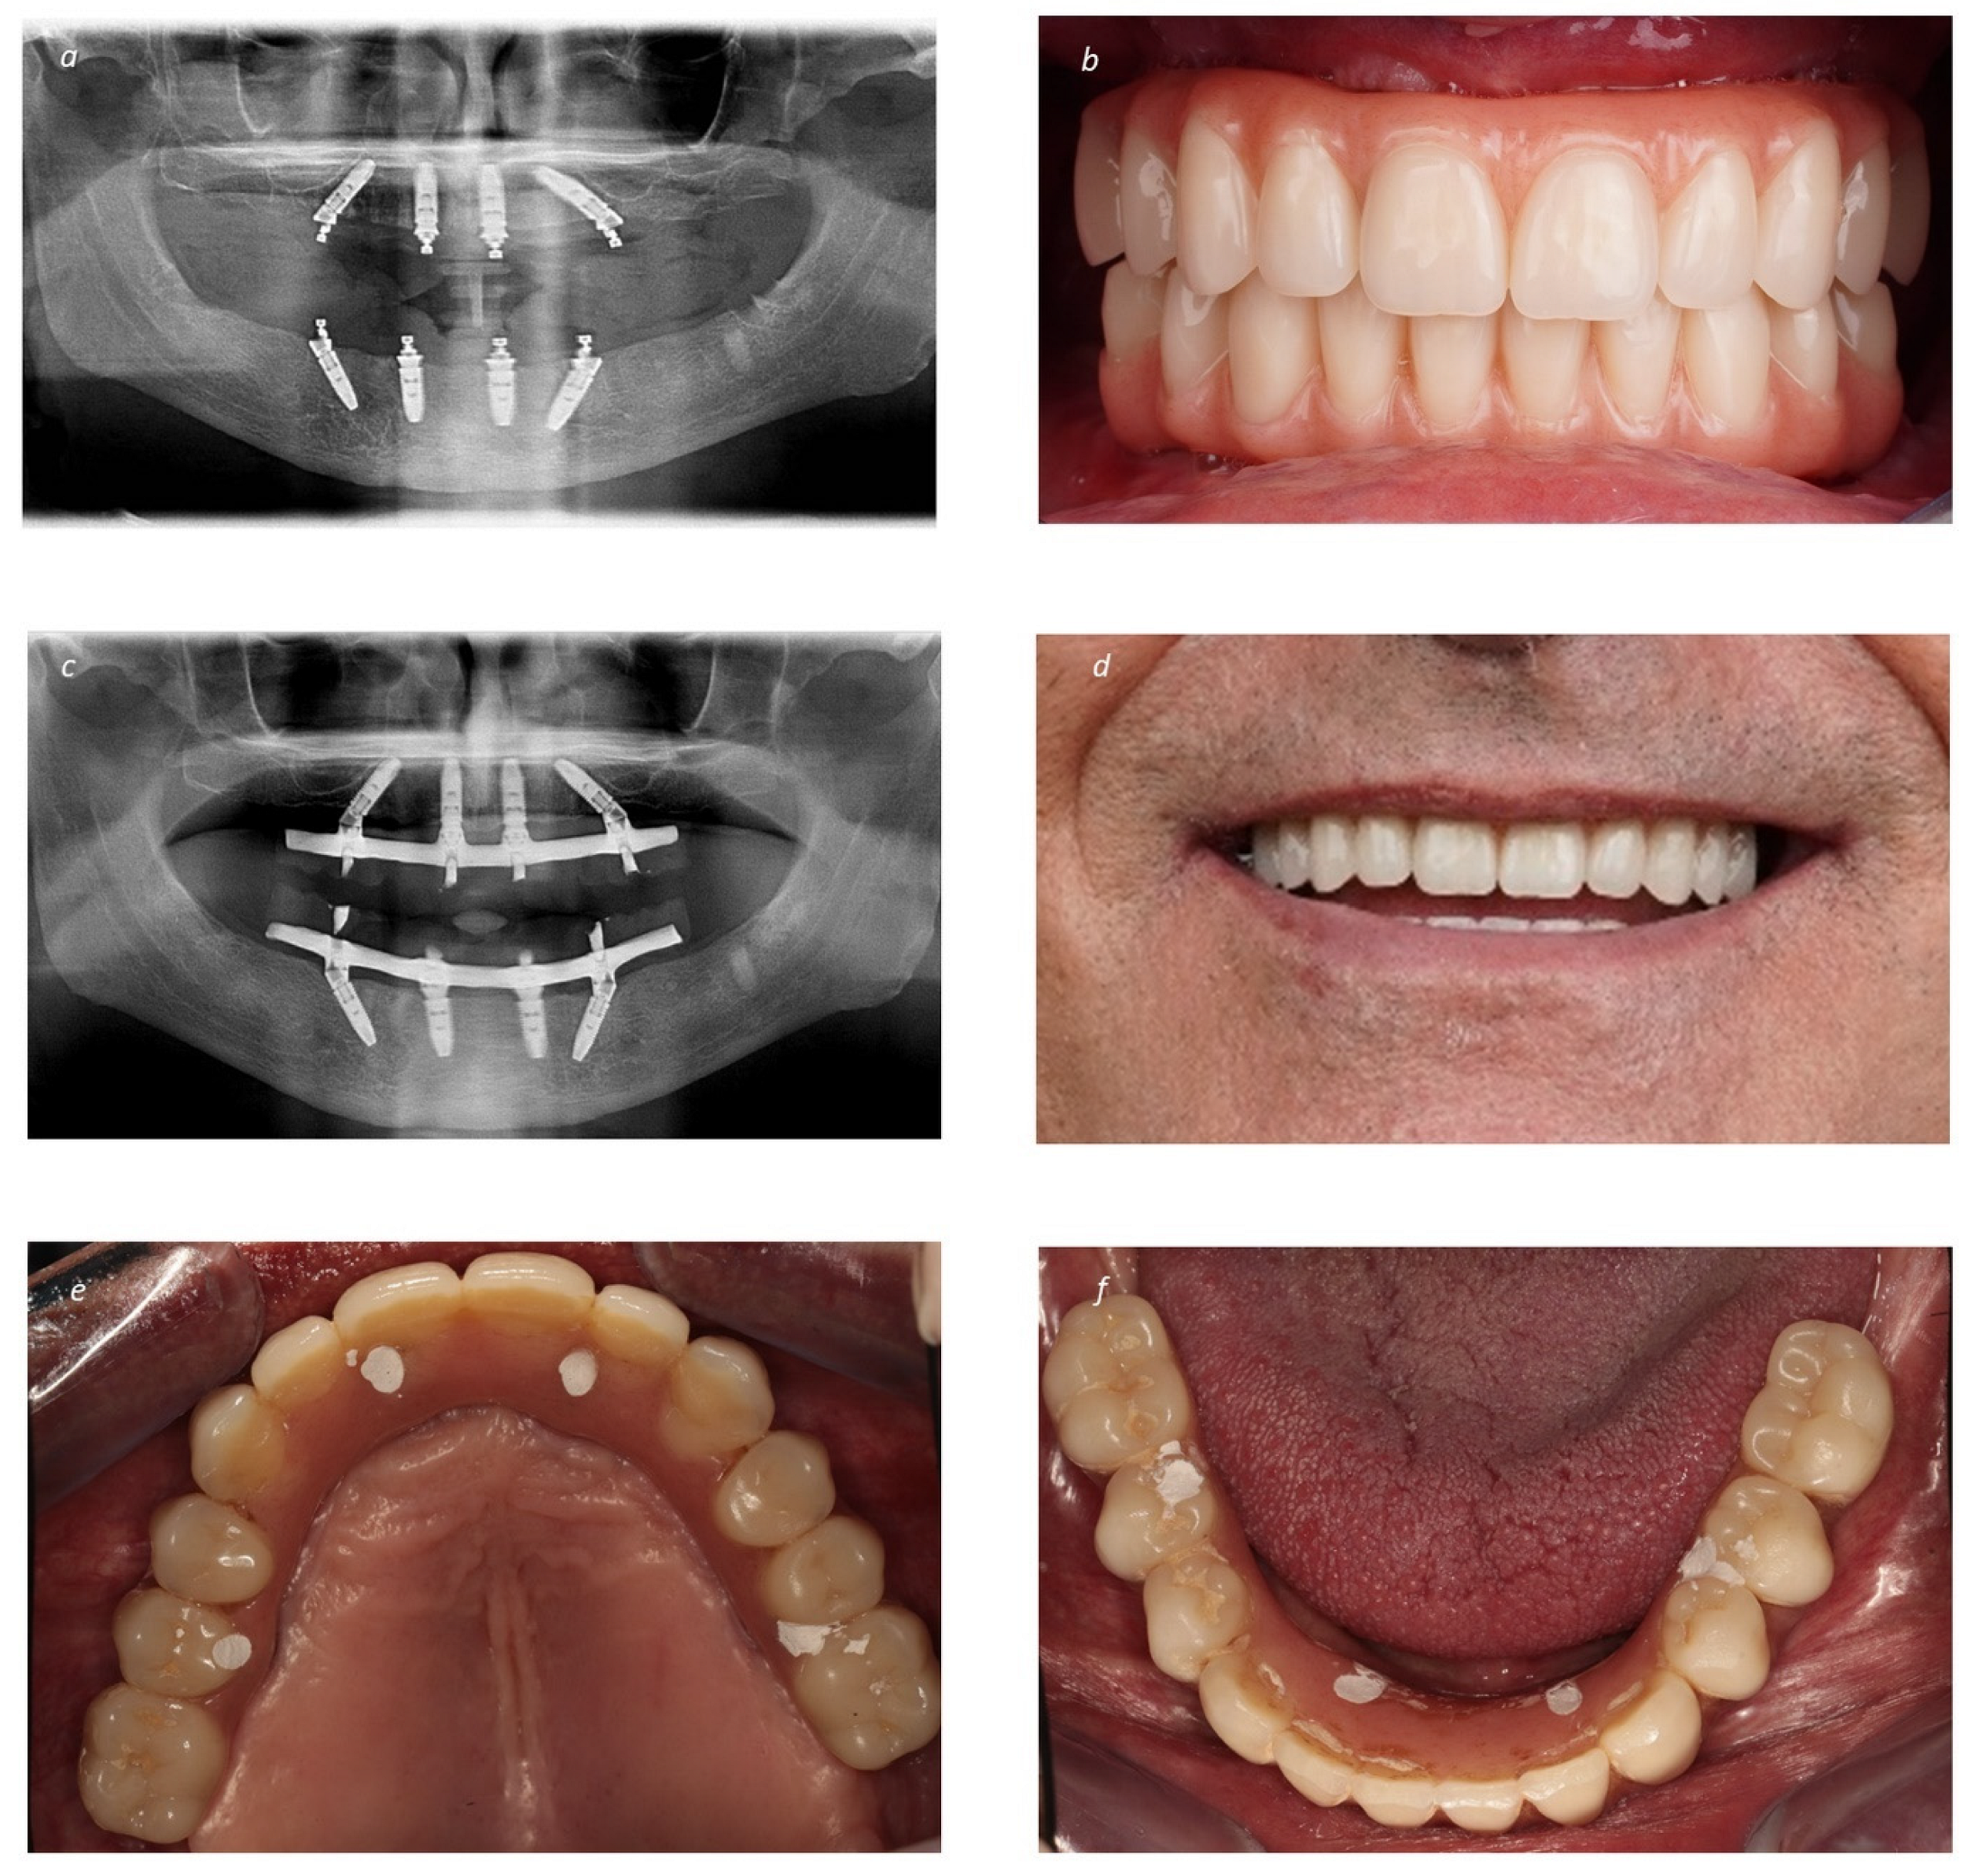

Figure 3.

Prosthetic restoration of the bimaxillary full-arch rehabilitation: (a) Post-operative orthopantomography immediately after surgery; (b) Intraoral frontal photograph with the immediate provisional prostheses; (c) Final orthopantomography at 2 years of follow-up with the definitive prostheses (Maló Clinic Acrylic Bridge—titanium infrastructure, acrylic artificial gingiva and acrylic crowns); (d) Patient smiling with the definitive prostheses in place at 2 years of follow-up; (e) Intraoral occlusal view of the maxillary definitive prostheses at 2 years of follow-up; (f) Intraoral occlusal view of the mandibular definitive prostheses at 2 years of follow-up.